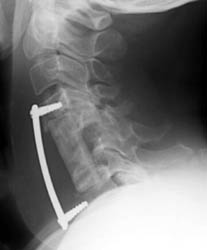

Immediate post-op radiograph demonstrate good position of the graft and fixation plate.

This is lateral radiograph taken several hours AFTER the incident with the food truck. Note the distal end of the fixation plate has loosened and is nearly completely out. The distal screws have minimal purchase in the C7 vertebral body.